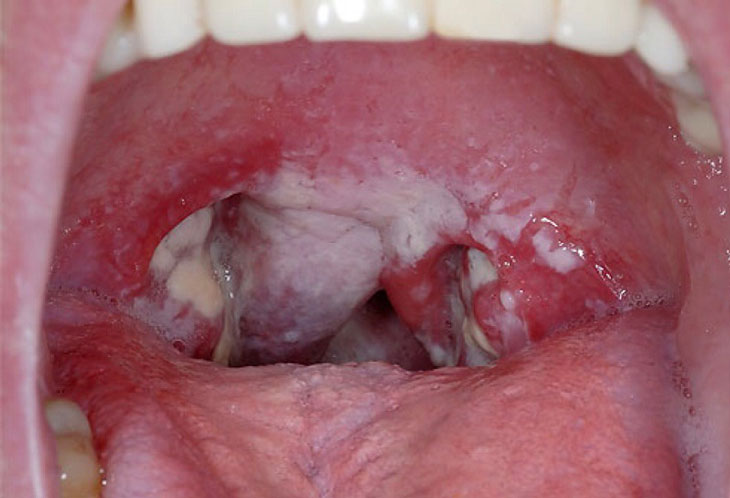

– Pseudomembranes on both sides of the throat, ivory white, gray, black, tough, sticky, bleeding easily.

Image of pseudomembranes on both sides of the throat, ivory white or gray in color in people with diphtheria